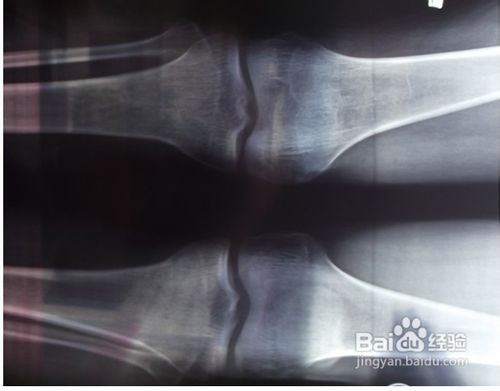

2、骨头闭合怎么长高?一个人要是骨头发育得好,这个人一定会长得比较高大。如果一个人的骨桌薜兀变头发育没有那么好,或者中途出了什么差错,这个人并不会长得太高,身材也会小个一些。在人体的所有骨头中,腿部尤其是膝盖部分的骨头和人体的长高关系最大。这个部分的骨头中间有一层很软的骨头叫做软骨。随着年龄的增长和人体的发育,软骨也会逐渐变硬或者骨化,一旦软骨完全成骨化的状态人就不太可能还可以增高了。可不可以控制软骨不要让它骨化呢?这是不可能的,随着年龄的增长长高,人体也会慢慢被骨化,一旦骨头闭合了,人的骨头生长发育也就停止了,人也就无法再长高。这是不可改变的事实,每个人都会经历相同的阶段,所以我们应该面对现实。